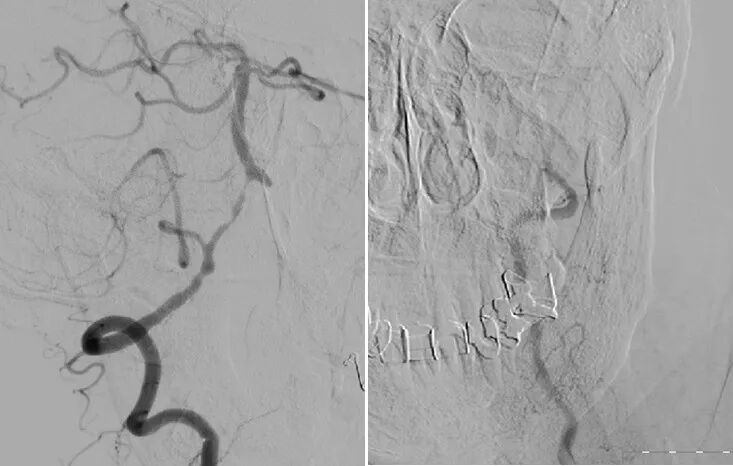

术前造影:

导丝怎么扩【载药时代 球扩天下】NOVA DES®颅内药物洗脱支架在椎动脉颅内段重度狭窄的应用二例_https://www.jmylbn.com_新闻资讯_第18张

左椎动脉+左颈动脉造影:

导丝怎么扩【载药时代 球扩天下】NOVA DES®颅内药物洗脱支架在椎动脉颅内段重度狭窄的应用二例_https://www.jmylbn.com_新闻资讯_第21张

右椎动脉造影:

导丝怎么扩【载药时代 球扩天下】NOVA DES®颅内药物洗脱支架在椎动脉颅内段重度狭窄的应用二例_https://www.jmylbn.com_新闻资讯_第24张

右椎动脉动脉正侧位:

导丝怎么扩【载药时代 球扩天下】NOVA DES®颅内药物洗脱支架在椎动脉颅内段重度狭窄的应用二例_https://www.jmylbn.com_新闻资讯_第29张

诊断

主要诊断:

1.右侧椎动脉V4段重度狭窄(90%);

2.高血压病2级 高危;

3.小脑梗死。